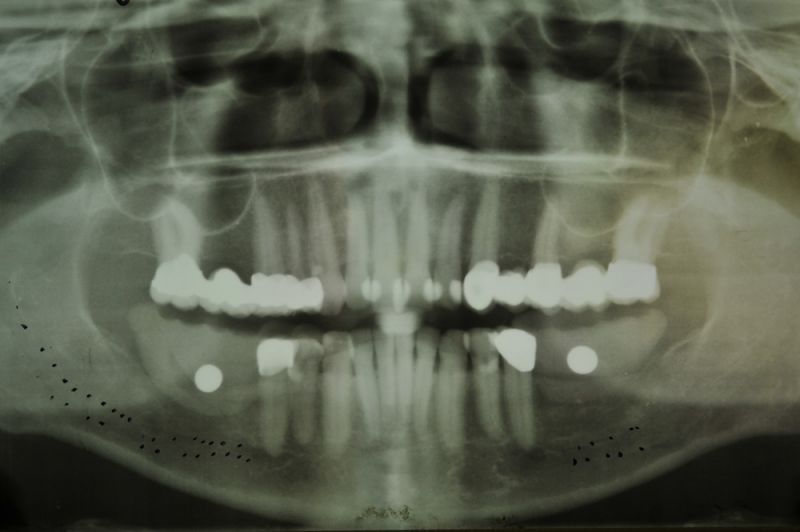

1. Notwendigkeit einer implantatgestützten Kronenversorgung mit der Vorgeschichte, dass die Patientin eine Vielzahl von Behandlern aufgesucht hatte, die eine Implantation im Unterkiefer als nicht durchführbar einschätzten.

2. Extrem schlechte knöcherne Verhältnisse im Unterkieferseitenzahnbereich, die sich intraoperativ noch einmal als ungünstiger darstellten, als bereits in den Voruntersuchungen erkennbar.

3. Sehr dünne Implantate, die von ursprünglich zwei je Kieferhälfte auf letztendlich drei je Kieferhälfte umgeplant werden mussten.